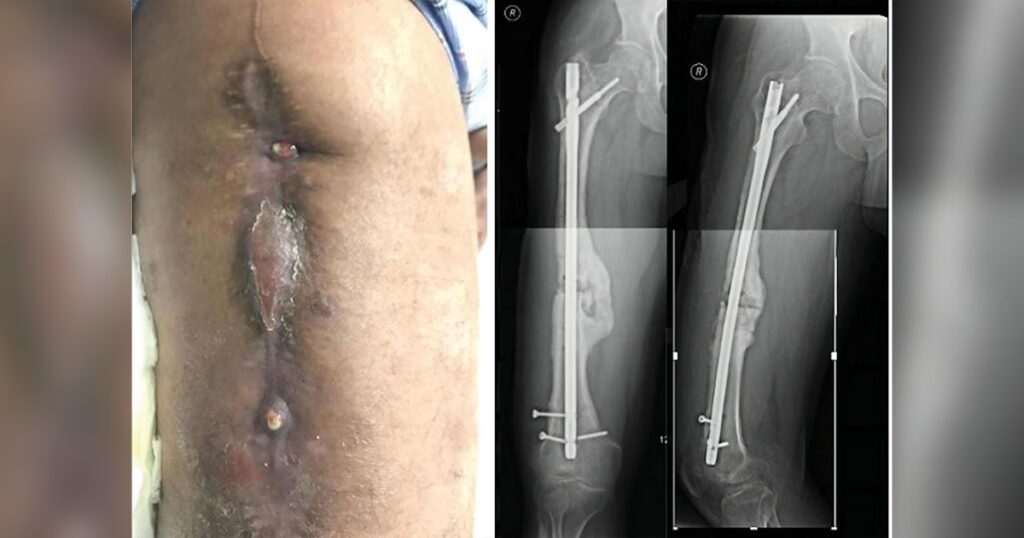

En frakturrelateret infektion opstår, når bakterier koloniserer området omkring et knoglebrud, som er blevet stabiliseret med implantater som skruer, plader eller søm. Disse infektioner kan føre til forsinket eller manglende heling af bruddet, kroniske smerter, tab af funktion og i værste fald amputation. Standardisering af diagnosen har tidligere været en udfordring, men for nylig er der udviklet internationale konsensuskriterier for at sikre en mere ensartet og præcis diagnosticering.

• Radiologiske tegn som løsning af implantater eller tegn på knoglenedbrydning.

• Radiologer: Tolker røntgenbilleder, CT- og MR-scanninger for at vurdere knogleheling og tegn på infektion.

Det primære mål med kirurgi er at opnå heling af bruddet, udrydde infektionen, hele bløddelene og genoprette lemmernes funktion. Valget af kirurgisk strategi afhænger stærkt af, om bruddet er helet eller ej.

Når Bruddet ER Helet

Hvis bruddet er solidt helet, er behandlingen relativt ligetil. Den består af en grundig kirurgisk rensning (debridement), hvor alt inficeret og dødt væv fjernes, og det interne fiksationsmateriale (plader, skruer) fjernes fuldstændigt. Dette efterfølges typisk af en antibiotikakur, ofte to uger intravenøst og fire uger i tabletform, for at forhindre, at infektionen udvikler sig til kronisk knoglebetændelse (osteomyelitis).

Når Bruddet IKKE er Helet

Dette er en mere kompleks situation, da implantatet stadig er nødvendigt for at stabilisere bruddet. Lægeteamet skal tage stilling til flere faktorer: